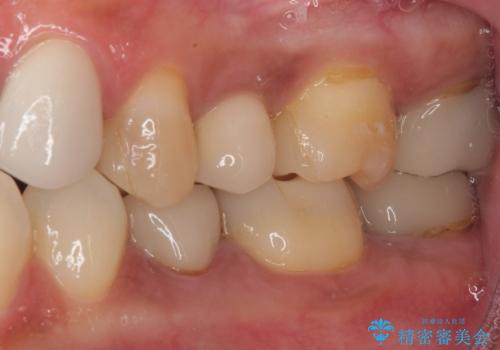

右下のむし歯が歯肉縁下に及んでおり、歯周外科処置(歯冠長延長術)を行った上で、根管治療を行い、状態を整えて補綴治療を行うこととしました。

上顎前歯の根尖病変に痛みがありましたが、既に前歯が補綴治療済みであっため、外科的歯内療法(歯根端切除術)を行うことで解決することとしました。